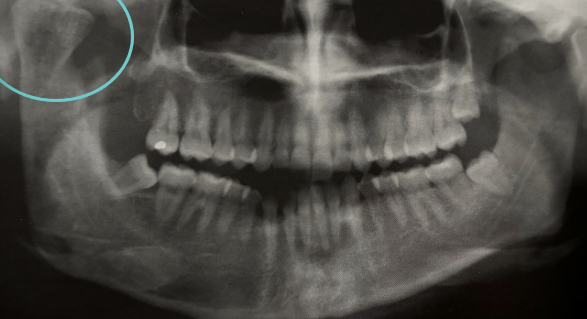

what is shown in the red circle

an artifact

how would you describe this radiographic lesion?

an apical well-defined radiopaque lesion